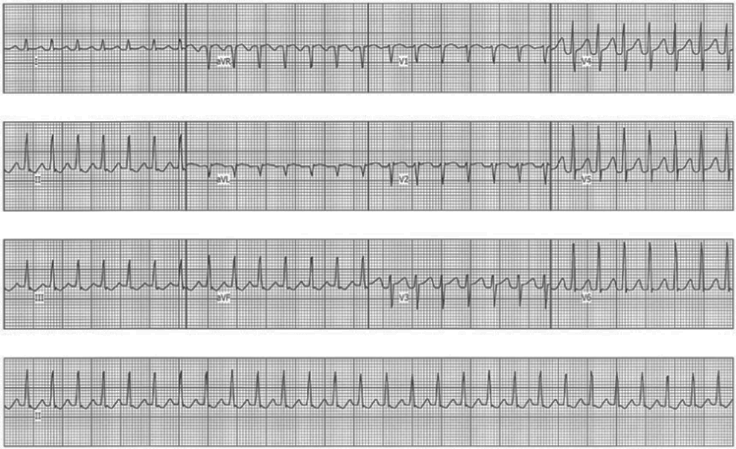

如图所示,该心电图显示的心律失常类型是( )。

A.室颤

B.阵发性房型心动过速

C.房室传导阻滞

D.阵发性室性心动过速

E.室性心动过速

正确答案是D